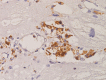

Background Glycosphingolipid accumulation in Fabry cells generates a proinflammatory response that may influence disease evolution and responsiveness to enzyme replacement therapy. This study evaluated incidence, mechanism, and impact of myocarditis in Fabry disease cardiomyopathy ( FDCM ). Methods and Results Myocarditis, defined as CD 3+ T lymphocytes >7/mm2 associated with necrosis of glycolipid-laden myocardiocytes, was retrospectively evaluated in endomyocardial biopsies from 78 patients with FDCM : 13 with maximal wall thickness (MWT) <11 mm (group 1), 17 with MWT 11 to 15 mm (group 2), 30 with MWT 16 to 20 mm (group 3), and 18 with MWT >20 mm (group 4). Myocarditis was investigated by polymerase chain reaction for cardiotropic viruses, by serum antiheart and antimyosin antibodies, and by cardiac magnetic resonance. Myocarditis was recognized at histology in 48 of 78 patients with FDCM (38% of group 1, 41% of group 2, 66% of group 3, and 72% of group 4). Myocarditis was characterized by positive antiheart and antimyosin antibodies and negative polymerase chain reaction for viral genomes. CD 3+ cells/mm2 correlated with myocyte necrosis, antimyosin autoantibody titer, and MWT ( P<0.001, r=0.79; P<0.001, r=0.84; P<0.001, r=0.61, respectively). Cardiac magnetic resonance showed myocardial edema in 24 of 78 patients (31%): 0% of group 1, 23% of group 2, 37% of group 3, and 50% of group 4. Conclusions Myocarditis is detectable at histology in up to 56% of patients with FDCM . It is immune mediated and correlates with disease severity. It can be disclosed by antiheart/antimyosin autoantibodies and in the advanced phase by cardiac magnetic resonance. It may contribute to progression of FDCM and resistance to enzyme replacement therapy.